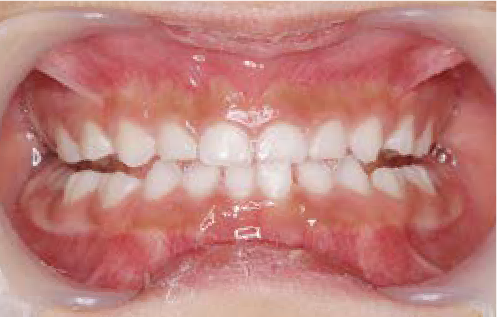

歯がガタガタに並んでいて、前歯の真ん中の位置が少し左にずれていました。

奥歯が生えるためのスペースが足りず、永久歯が生えて来られない状況が確認できました。

また、飲み込むとき下くちびるに力が入ってしまうクセが見られ、お顔全体の成長が遅れている様子が確認できました。

治療を終えて

歯がきれいに生えるためのスペースをしっかり確保することができ、歯並びを乱していたお口のクセも改善されたため、奥歯が生えるスペースを確保することができました。

しっかり噛めるかみ合わせを作ることが、将来の健康につながるので「よく噛む」練習も続けてもらっています。

主訴・治療内容 歯がガタガタになってきたことに悩み、無料相談に来院されました。

治療期間 3年

費用 462,000円(税込)